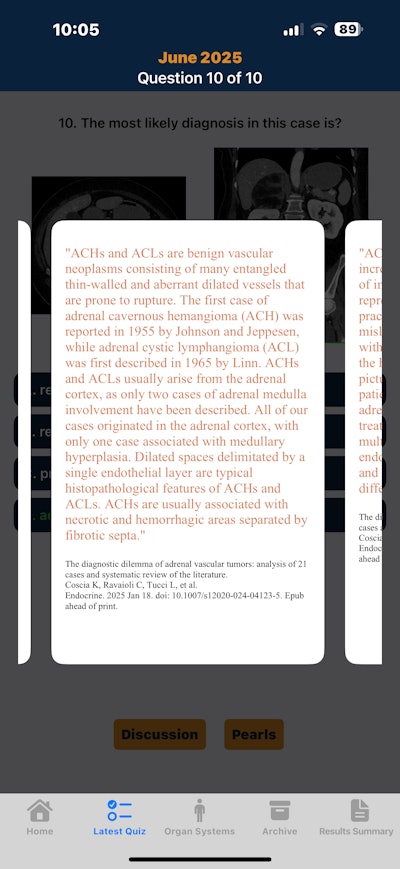

CTisus iQuiz 25, Elliot Fishman, MD, (iOS)

The popular radiology quiz app is in the hunt for its second Minnie for Best Educational Mobile App.Elliot Fishman, MD.

The popular radiology quiz app is in the hunt for its second Minnie for Best Educational Mobile App.Elliot Fishman, MD.

Our second finalist is also a familiar one. The winner of the Minnies award for Best Educational Mobile App in 2020 under its previous name CTisus iQuiz, CTisus iQuiz 25 was renamed to highlight the many recent updates and upgrades to the radiology quiz app, according to Elliot Fishman, MD, of Johns Hopkins University.

“We spent so much time developing new content and improving the site, I thought an update of the name would be good,” Fishman told AuntMinnie.

The app currently provides over 1,800 magnificent cases in 15 anatomical regions. Quiz cases feature audio discussions and imaging pearls.

In the five years since iQuiz 25 won its Minnies award, the app has been upgraded to a universal app for both iPhone and iPad. Over 300 new cases have been added, and the user interface has been improved to deliver a smoother and more pleasant experience for the users, Fishman said.